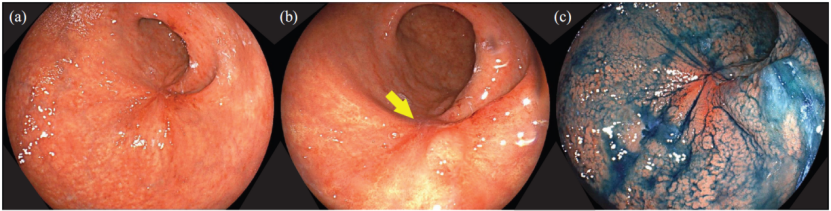

胃镜 胃窦大弯侧可见Borrmann III型胃癌(图1)。

图1. 上消化道内镜检查(a,b)显示胃窦大弯侧Borrmann III型胃癌

治疗开始后第56天: CT显示原发病灶明显缩小,腹膜种植征象消失,疗效评估为部分缓解(PR)。同期内镜检查示胃原发病灶较前缩小,未见活动性出血或肠道狭窄(图3)。

图3. 上消化道内镜检查显示原发病灶整体缩小,部分区域伴有溃疡形成(箭头)

治疗开始后第5个月: CT评估显示,原发病灶及转移灶完全消失(cCR)。同期胃镜检查显示,胃原发病灶消失,呈瘢痕化(图4)。根据《日本胃癌分类第15版》 [2] 关于内镜下完全缓解 (eCR)——所有肿瘤消失,并且活检未检测到癌细胞——原发病灶疗效评估为eCR。

图4. 上消化道内镜检查显示原发病灶已经消失,并且可以观察到相对平滑的黏膜(箭头)。从瘢痕化的原发病灶处获得的活检标本显示仅存在炎性细胞,未发现肿瘤细胞